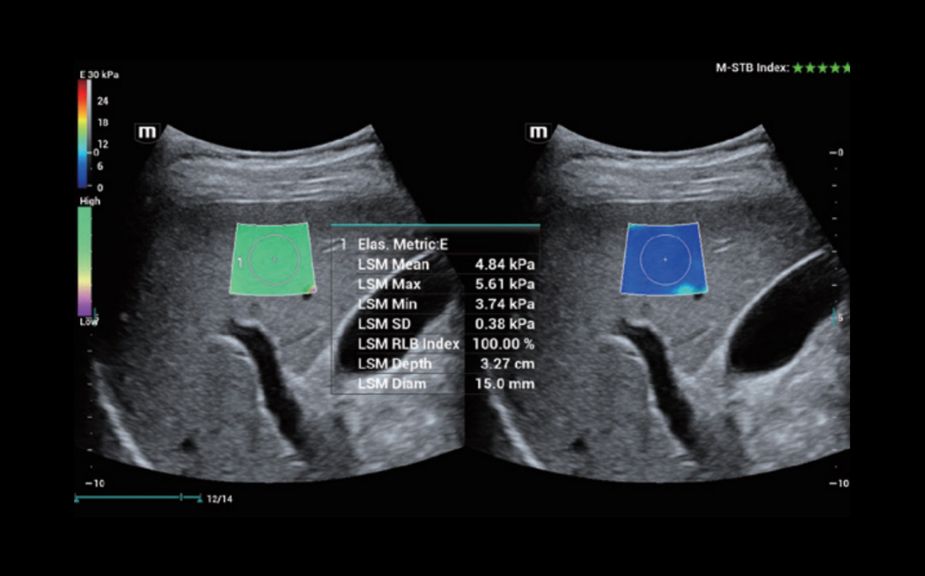

HiFR STE печени

Инновационная оценка жесткости: HiFR STE

В 10 раз более высокая частота кадров при работе режима STE

Высокая чувствительность к движению для повышения стабильности и точности

HiFR STE печени